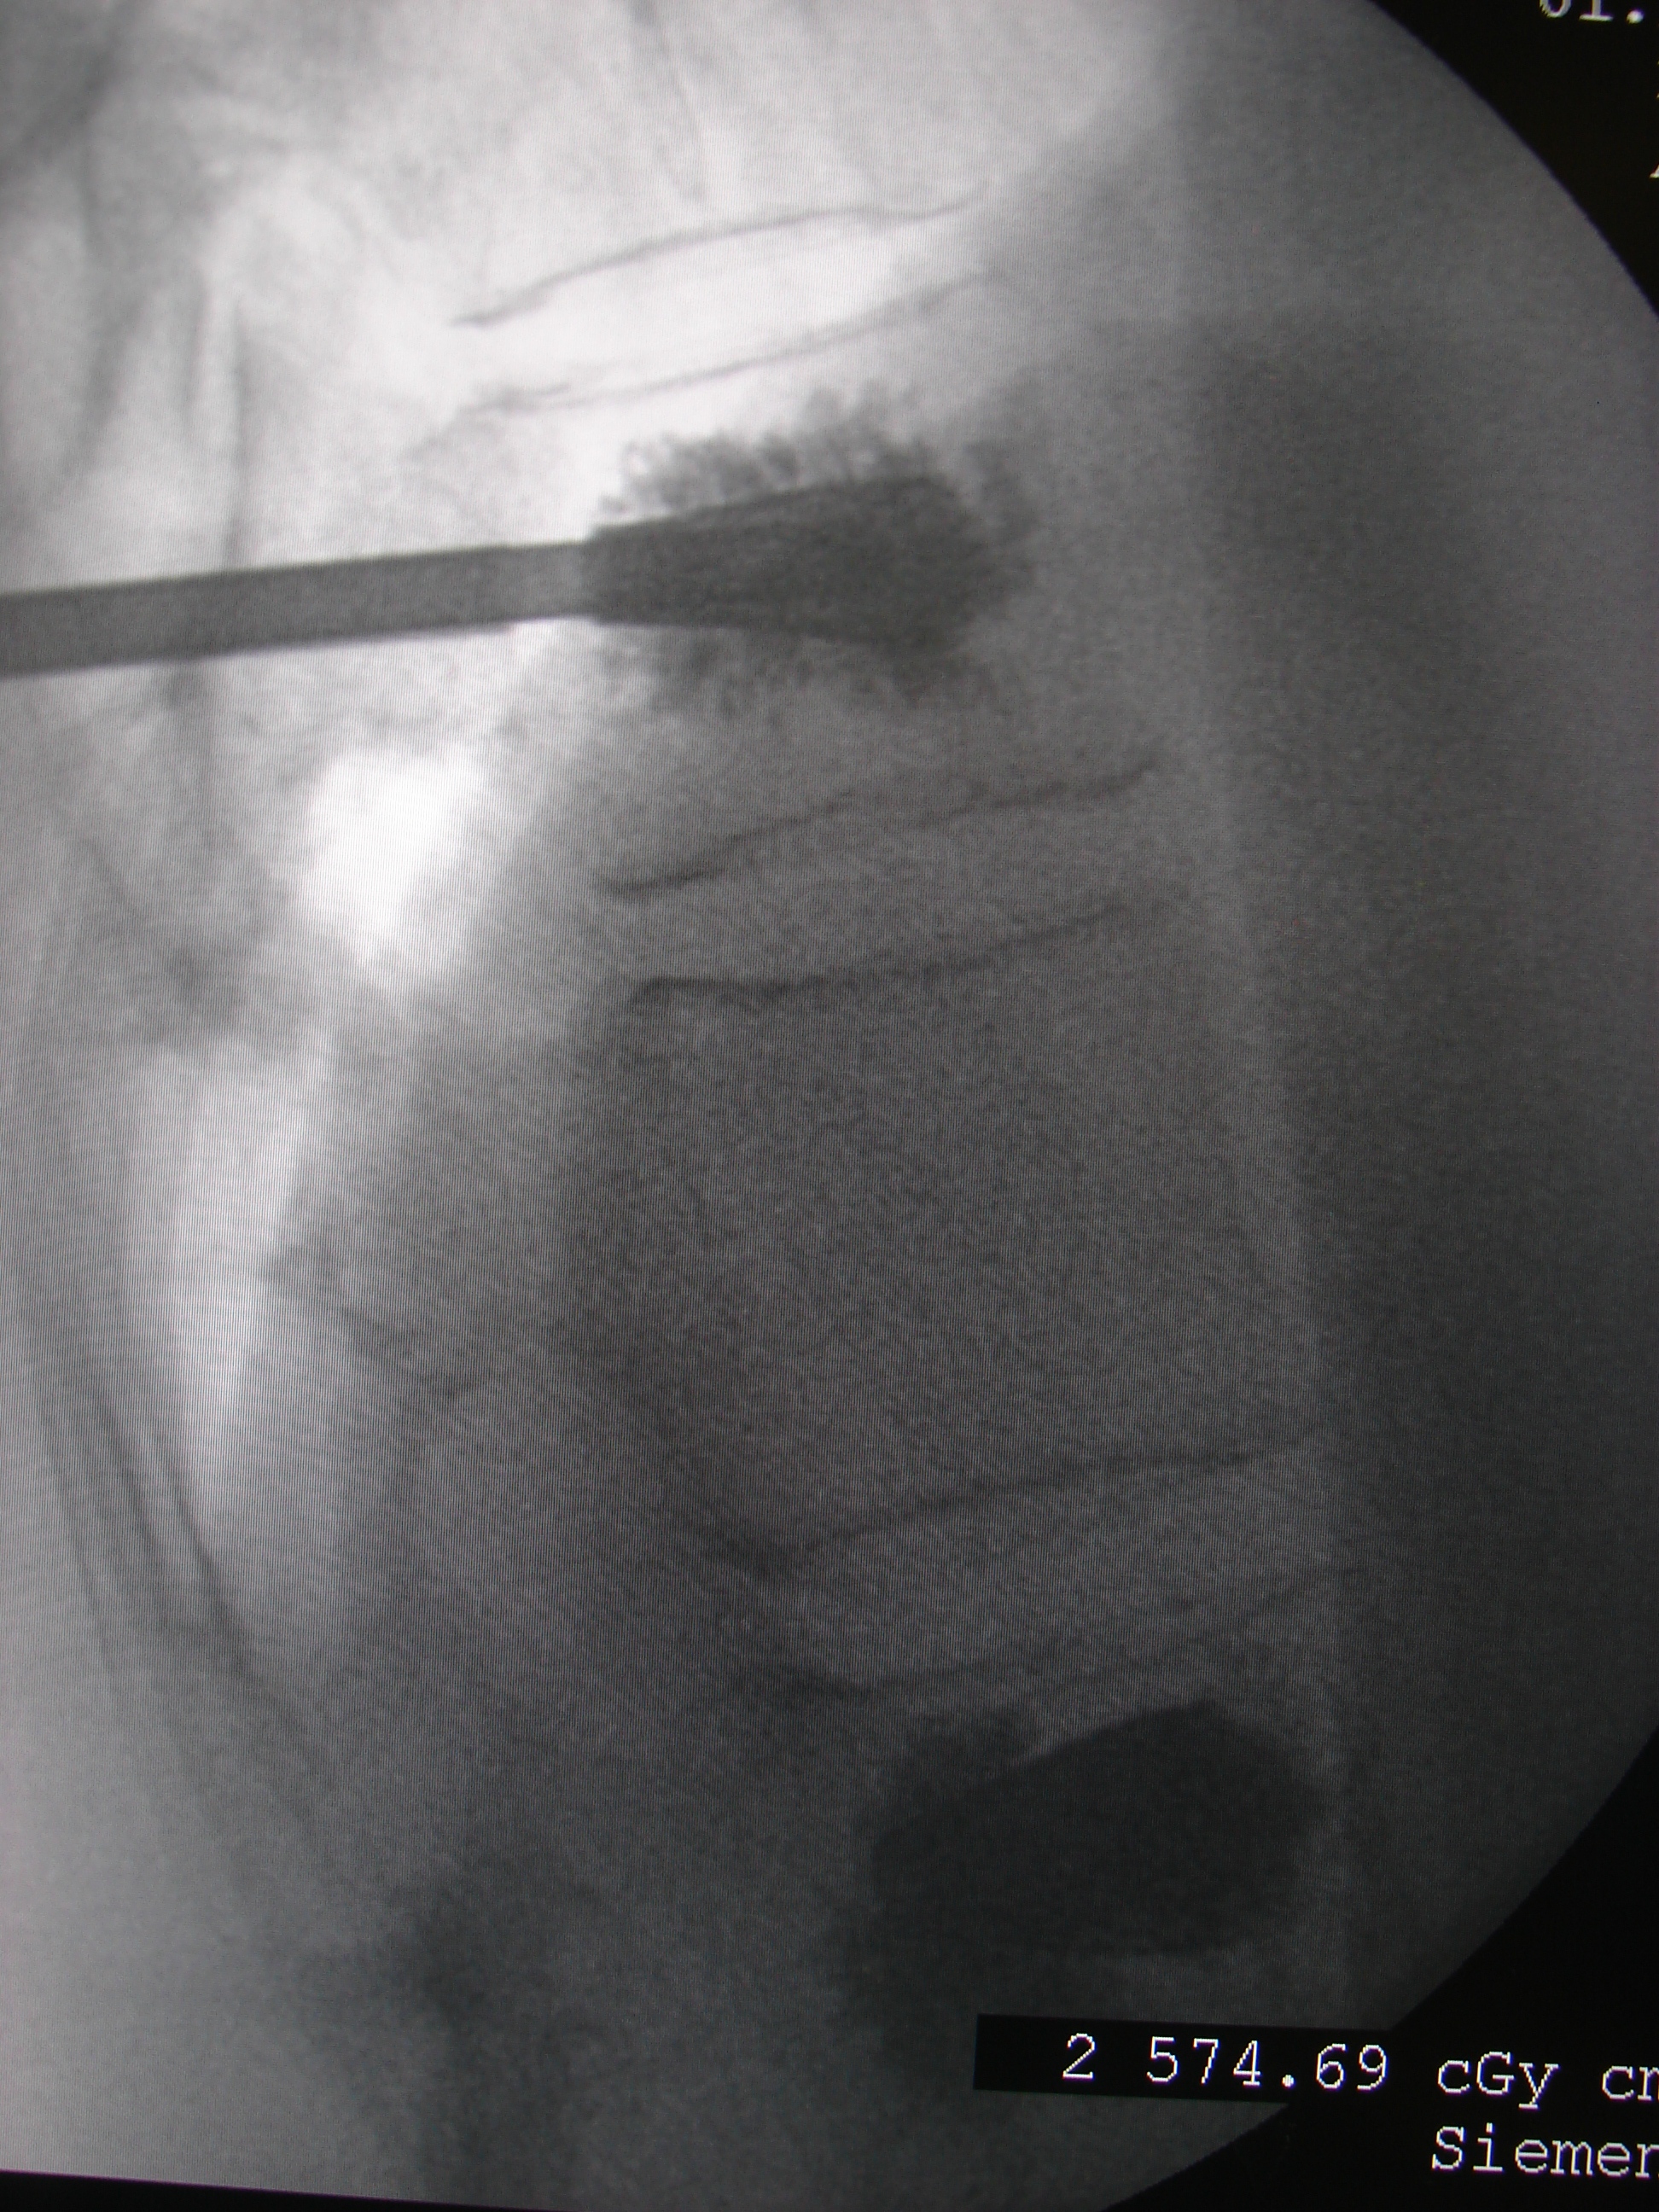

Δια την αντιμετώπιση των επωδύνων σπονδυλικών μεταστάσεων, πραγματοποιήθηκε ενίσχυση των σπονδυλικών σωμάτων με Methylmethacrylate (P.M.M.P.).

Με τη τεχνική αυτή ταχύτατα η πάσχουσα απαλλάχθηκε απο τον πόνο.

Εικόνα 6: α, β, γ, δ